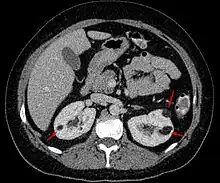

Angiomyolipoma in both kidneys (arrows) in computer tomography. The tumours are hypodense (dark) due to fat content.

CT scan of a renal angiomyolipoma. It involves the renal cortex, and has an attenuation of less than 20 HU on the Hounsfield scale, which are typical characteristics.[2]